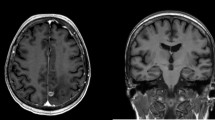

3D T1-weighted MRI images were collected from 55 patients with tumors infiltrating the left (HipL, n = 27) or right (HipR, n = 28) hippocampus, along with 30 age- and sex-matched healthy controls (HC). Gray matter volume differences of the contralesional hippocampal regions and three control regions (superior frontal gyrus, caudate nucleus, and superior occipital gyrus) were evaluated using voxel-based morphometry (VBM) analyses. Volumetric differences in the hippocampus and its subregional volume were measured using the FreeSurfer software.

Compared with HC, patients with unilateral hippocampal glioma exhibited significantly larger gray matter volume in the contralesional hippocampus and parahippocampal regions (cluster = 571 voxels for HipL; cluster 1 = 538 voxels and cluster 2 = 88 voxels for HipR; family-wise error corrected p < 0.05). No significant alterations were found in control regions. Volumetric analyses showed the same trend in the contralesional hippocampal subregions for both patient groups, including the CA1 head, CA3 head, hippocampus amygdala transition area (HATA), fimbria, and the granule cell molecular layer of the dentate gyrus head (GC-ML-DG head). Notably, the differences of the contralesional HATA (HipL: η2 = 0.418, corrected p = 0.002; HipR: η2 = 0.313, corrected p = 0.052) and fimbria (HipL: η2 = 0.450, corrected p < 0.001; HipR: η2 = 0.358, corrected p = 0.012) still held after the Bonferroni correction.